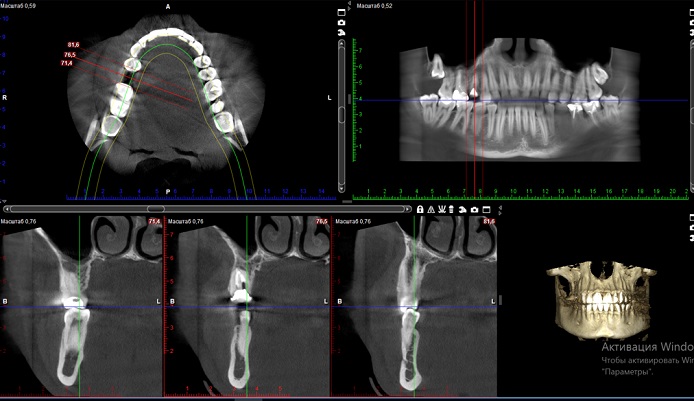

Перший візит до стоматолога майже завжди супроводжується потребою зробити комп’ютерну томографію (КТ). Це сучасний метод діагностики, який дозволяє дізнатись про особливості будови щелеп та зубного ряду, та виявити приховані патології різного роду.

КТ потрібна для отримання детальної картини стану зубо-щелепного апарату, постановки точного діагнозу. Від цього залежить підбір та ефективність лікування.